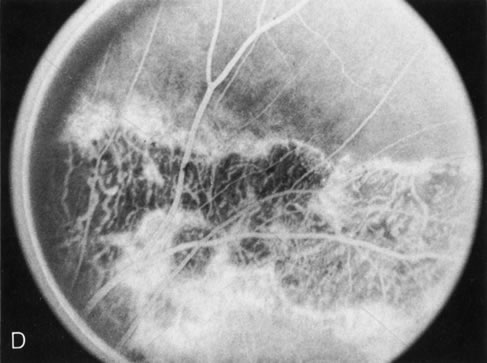

Fig. 4. Choroideremia and choroideremia carrier. A. The choroidal atrophy in this affected male is not apparent in the fundus. B. However, the angiogram shows diffuse atrophy of the choriocapillaris with persistent visualization of the larger choroidal vessels. C. This carrier female has peripapillary choroidal atrophy and diffuse pigment mottling. D. The patchy areas of focal choroidal atrophy that occasionally occurs in carriers is evident on angiography.

The typical carrier female, with focal or diffuse pigment mottling, does not show choroidal atrophy. However, a few carrier females have a more severe form with focal areas of choroidal atrophy. The presence of these areas, and possible progression, can be documented by FA (Fig. 4C and D). These carriers exhibit a mosaicism, which is explained by the Lyon hypothesis of random X-chromosome inactivation.